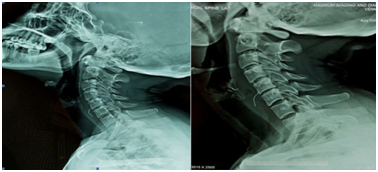

The patient was further advised CT scan which revealed a 2.7 cm linear well defined foreign body with metallic density in the retropharyngeal space at the C5- C6 level (Figure 3). It was localized to be in the left paramedian aspect, superior and posterior to left lobe of thyroid gland and extending posterior to the carotid sheath at that level. A collection of size 3.5 x 3.2 cm superior to the left lobe of thyroid gland was seen.

Figure 3 CT scan showing the foreign body.

The patient was planned for a neck exploration by an external approach. A vertical incision was given along the anterior border of the sternocleidomastoid from the level of hyoid bone superiorly to the cricoid cartilage inferiorly. The deep fascia was incised along the anterior border of the sternocleidomastoid muscle. The dissection was continued in the paralaryngeal tunnel. Pus collected in the superior pole of the left lobe of thyroid gland pus collected was drained (Figure 2). A sample of pus obtained was sent for culture and sensitivity. On further dissection, the foreign body was seen in horizontal orientation, embedded in the soft tissues medial to the carotid sheath and deep to the superior lobe of the thyroid gland (Figure 3). The foreign body was retrieved and was found to be a metal wire of length 2.7 cm (Figure 5). Post operative course was uneventful and the patient was discharged after five days.